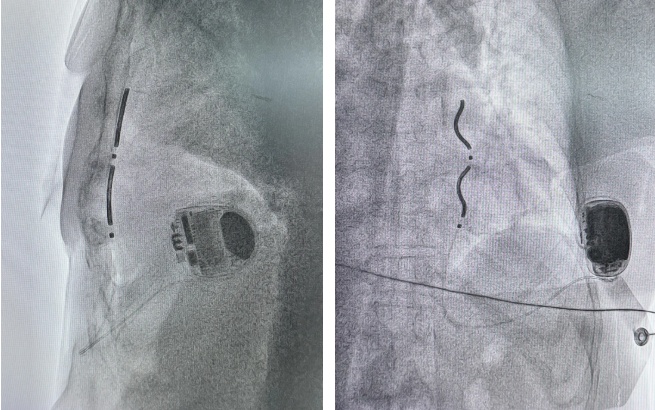

为确保手术万无一失,心血管科曲新凯主任、孔琤琦副主任医师联合麻醉、心外、胸外团队进行了多轮详细讨论。他们利用患者术前的胸部CT,三维重建其胸腔结构,精确规划电极植入路径,推敲每一个手术细节,做好了充分预案。

手术当日,在麻醉团队的有力保障下,多学科专家紧密协作。手术过程顺利,电极放置稳定,各项电学参数良好,除颤测试一次成功。术后第一天,患者即转回普通病房,恢复良好。